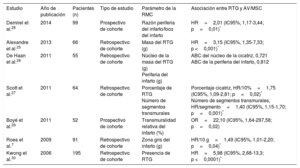

Estudios que informan del riesgo de arritmias ventriculares o muerte súbita cardiaca asociado con el realce tardío de gadolinio en pacientes con enfermedad coronaria

| Estudio | Año de publicación | Pacientes (n) | Tipo de estudio | Parámetro de la RMC | Asociación entre RTG y AV/MSC |

|---|---|---|---|---|---|

| Demirel et al.28 | 2014 | 99 | Prospectivo de cohorte | Razón periferia del infarto/foco del infarto | HR=2,01 (IC95%, 1,17-3,44; p=0,01)* |

| Alexandre et al.25 | 2013 | 66 | Retrospectivo de cohorte | Masa del RTG (g) | HR=3,15 (IC95%, 1,35-7,33; p <0,001)* |

| De Haan et al.26 | 2011 | 55 | Retrospectivo de cohorte | Núcleo de la masa del RTG (g) Periferia del infarto (g) | ABC del núcleo de la cicatriz, 0,721 ABC de la periferia del infarto, 0,812 |

| Scott et al.27 | 2011 | 64 | Retrospectivo de cohorte | Porcentaje de RTG Número de segmentos transmurales | Porcentaje cicatriz, HR/10%=1,75 (IC95%, 1,09-2,81; p=0,02)* Número de segmentos transmurales, HR/segmento=1,40 (IC95%, 1,15-1,70; p=0,001)* |

| Boyé et al.29 | 2011 | 52 | Prospectivo de cohorte | Transmuralidad relativa del infarto (%) | OR=22,10 (IC95%, 1,64-297,58; p=0,02) |

| Roes et al.7 | 2009 | 91 | Retrospectivo de cohorte | Zona gris del infarto (g) | HR/10 g=1,49 (IC95%, 1,01-2,20; p=0,04)* |

| Kwong et al.30 | 2006 | 195 | Retrospectivo de cohorte | Presencia de RTG | HR=5,98 (IC95%, 2,68-13,3; p <0,0001)* |

ABC: área bajo la curva; AV: arritmias ventriculares; HR: hazard ratio; IC95%: intervalo de confianza del 95%; MSC: muerte súbita cardiaca; OR: odds ratio; RMC: resonancia magnética cardiaca; RTG: realce tardío de gadolinio.